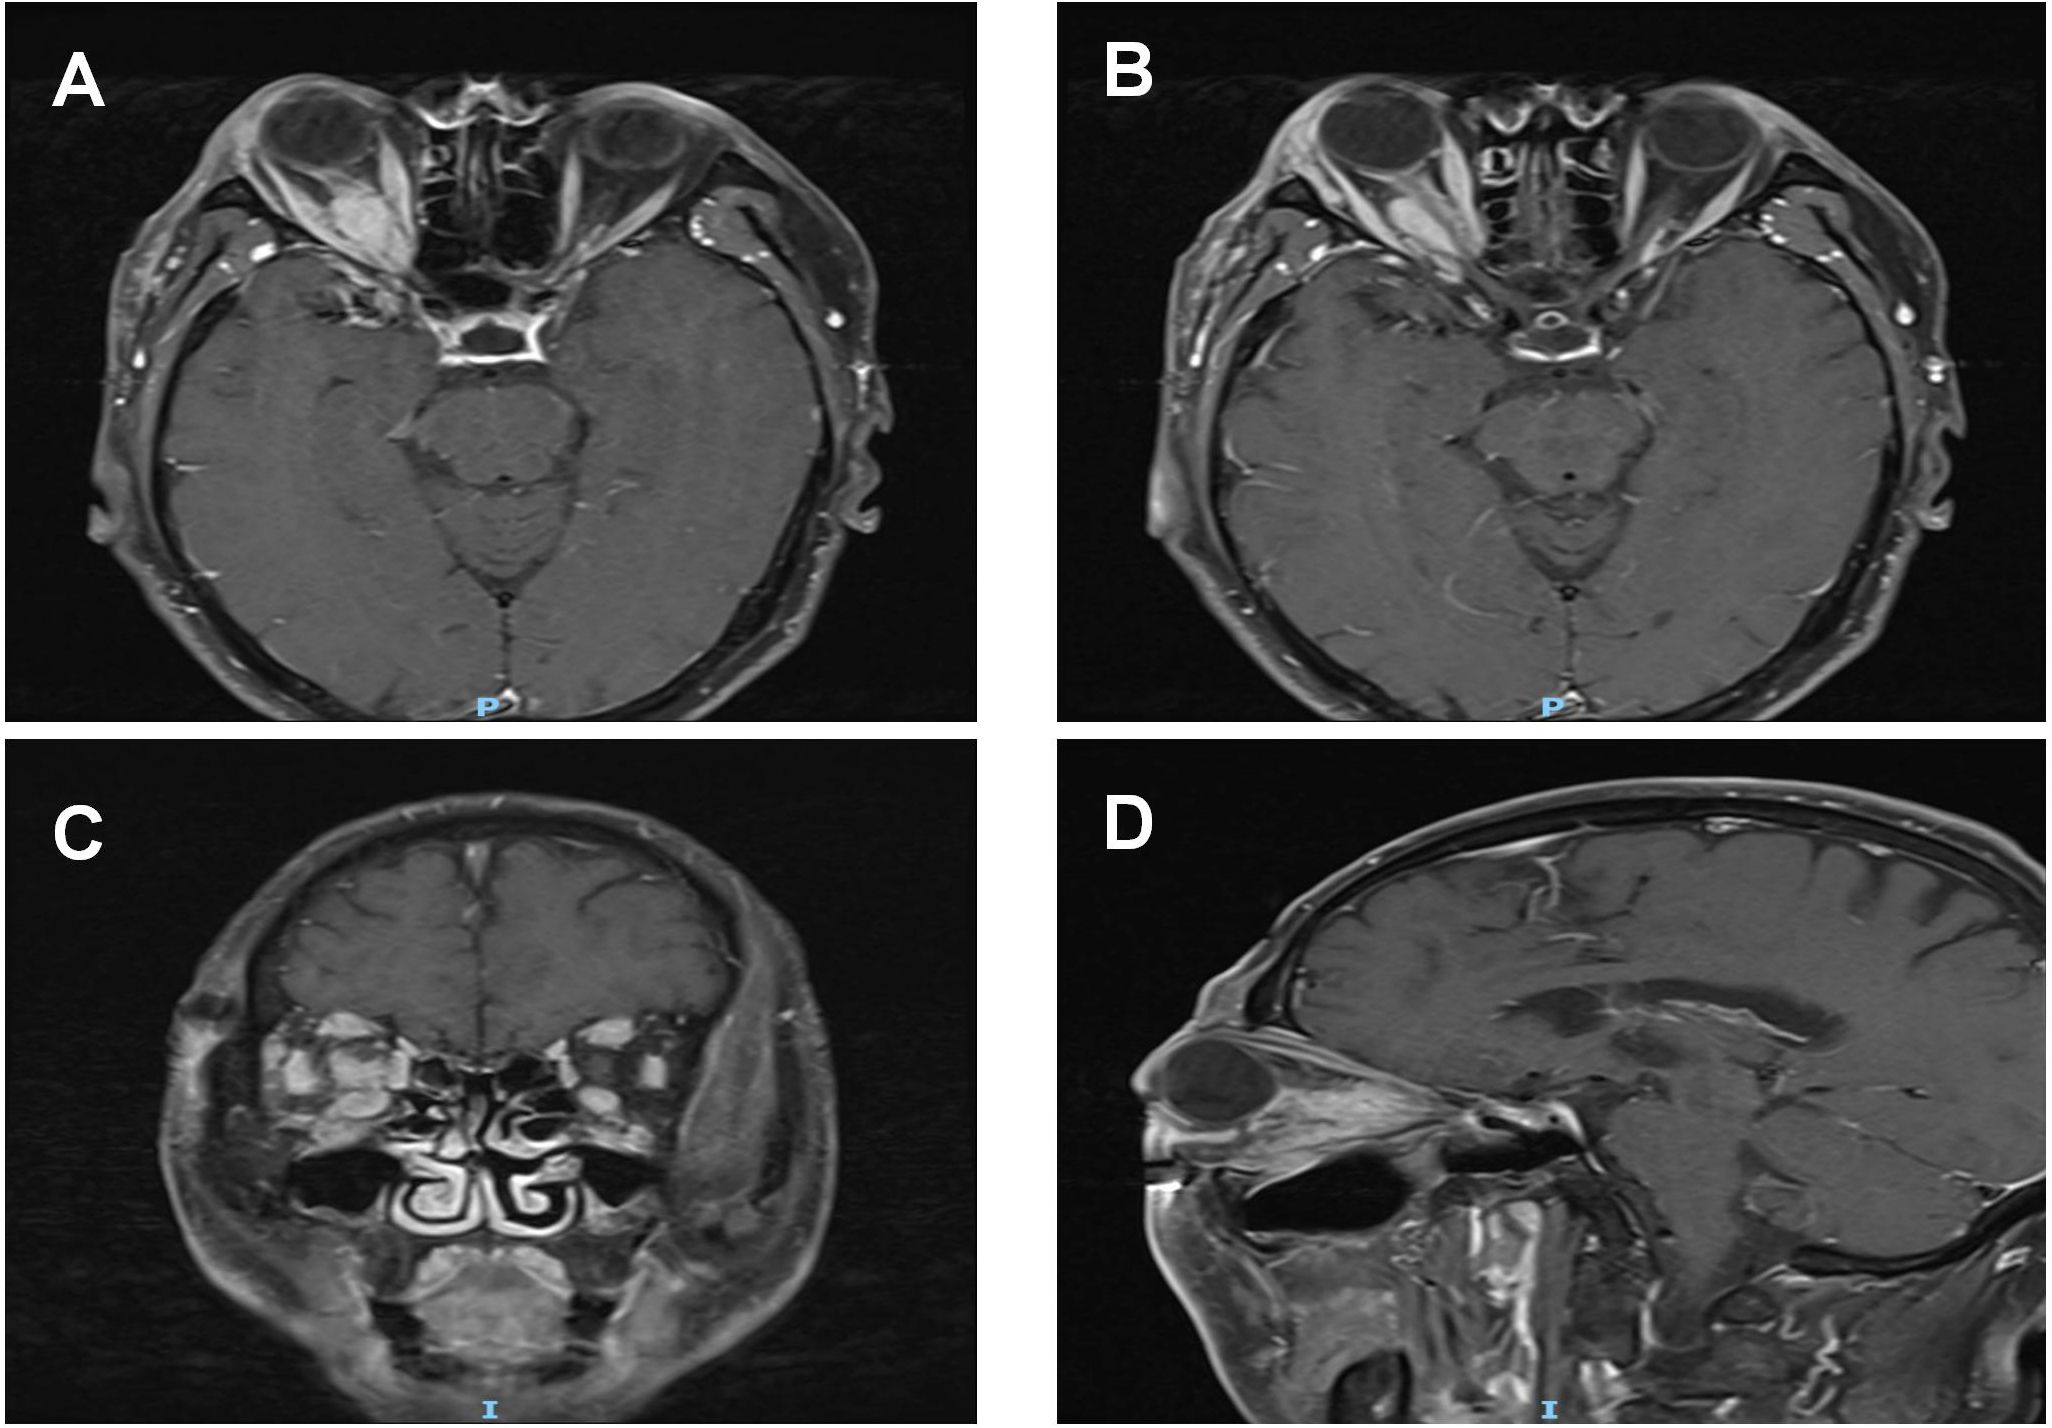

Figure 2

Pre-treatment MRI orbital plain scan + contrast enhancement: (A, B) A spindle-shaped soft tissue mass (long diameter: 20 mm × short diameter: 12 mm) is visible from the intracanalicular segment to the intraorbital segment of the right optic nerve. On T1WI, the mass exhibits isointense to hypointense signals with ill-defined borders; it surrounds the optic nerve without invading the optic nerve parenchyma, and no optic nerve transection or eccentric compression is observed. The bellies of the right medial rectus and lateral rectus muscles show symmetric thickening, presenting isointense signals on T1WI. Their tendon insertion sites are clear, and moderate homogeneous enhancement is seen on contrast-enhanced scan, with no "swelling at the myotendinous junction".The right lacrimal gland displays diffuse enlargement, showing isointense signals on T1WI and homogeneous enhancement after contrast administration. (C, D) T1WI coronal and sagittal images, respectively.The mass, thickened extraocular muscles, and lacrimal gland all present moderate homogeneous enhancement, with an enhancement degree lower than that of blood vessels. No "ring enhancement" or "necrotic area" is noted. The mucosa of the bilateral maxillary sinuses and ethmoid sinuses is thickened with mild enhancement.

The bellies of the right medial rectus and lateral rectus muscles show symmetric thickening, presenting isointense signals on T1WI. Their tendon insertion sites are clear, and moderate homogeneous enhancement is seen on contrast-enhanced scan, with no “swelling at the myotendinous junction”. The right lacrimal gland displays diffuse enlargement, showing isointense signals on T1WI and homogeneous enhancement after contrast administration. C, D: T1WI coronal and sagittal images, respectively. The mass, thickened extraocular muscles, and lacrimal gland all present moderate homogeneous enhancement, with an enhancement degree lower than that of blood vessels. No “ring enhancement” or “necrotic area” is noted. The mucosa of the bilateral maxillary sinuses and ethmoid sinuses is thickened with mild enhancement.